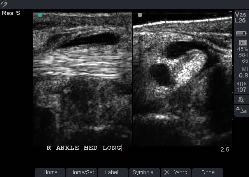

Pathological Ankle and Foot Images